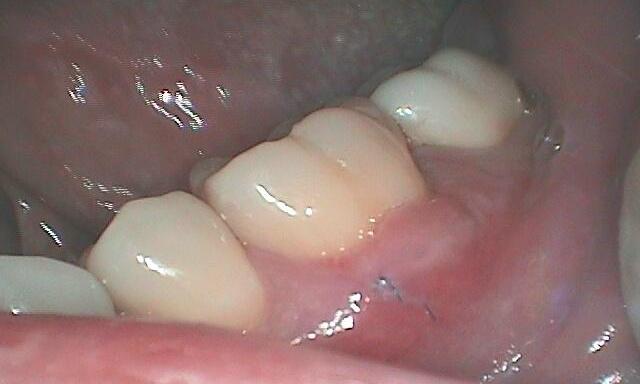

If the damage is too significant, we need to perform a more extensive procedure to help repair the damage. And if it goes beyond there, the chances of saving the tooth become slim; then we start talking about dental implants to replace that tooth.

Unfortunately (like this actual patient shown in the picture) we need to remove the tooth.